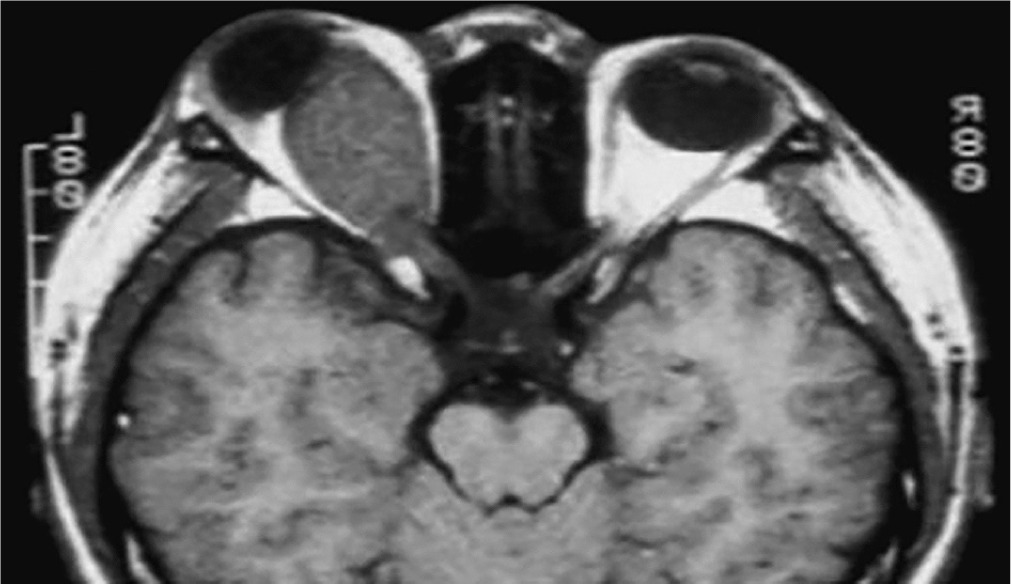

Neurofibromatosis type 1 (von Recklinghausen disease) is a phakomatosis caused by a mutation in the NF1 gene located on chromosome 17q11.2. This gene encodes the protein neurofibromin, which is responsible for regulating cell division and proliferation [5, 6]. The traditional designation of these abnormalities as von Recklinghausen disease is now considered largely historical. The disease has an estimated prevalence of approximately 1 : 3,500 live births and affects 1 : 4,000 to 1 : 5,000 individuals in the general population [4, 8, 9]. Neurofibromatosis type 1 is inherited in an autosomal dominant manner, although more than half of cases occur sporadically, representing new mutations [9]. In most children, the new mutation is inherited from a parent. The risk that a child of an affected parent will develop neurofibromatosis type 1 is approximately 50%. A characteristic feature of the disease is the appearance of pigmented patches on the skin, referred to as café-au-lait spots. The presence of at least five to six such spots, covering any region of the child’s body, is indicative of the disease. Freckles and areas of hyperpigmentation are also observed in regions with limited light exposure, such as the axillae, groin, and beneath the breasts in women (Crowe’s sign). Also, diffuse neurofibromas occur in the skin, brain, and spinal cord. The primary distinguishing feature of changes in the eyeball is the presence of Lisch nodules on the iris and other characteristic ocular features of this syndrome [10–12]. Lisch nodules arise as a result of developmental disturbances and uncontrolled divisions of mast cells and pigment epithelium forming the outer surface of the iris [8, 10, 11] (Figure 4). They are a consequence of damage to the choroidal melanocytes and, histologically, correspond to melanocytic hamartomas of the iris. A diagnosis is warranted by the presence of at least two Lisch nodules. The role of solar radiation in their development remains controversial [12]. Lisch nodules are visible on slit-lamp examination as small, vascularized, elevated structures of the iris, measuring 0.1 mm to 2 mm in size, in various shades of brown. Their position within the iris crypts can occasionally make them difficult to detect. Lisch nodules occur in 10% to 90% of children with this syndrome, and their number increases with age. The nodules do not affect visual acuity, but when they are numerous and asymmetrically distributed between the eyes, they may lead to cosmetic concerns. Glaucoma in neurofibromatosis type 1 coexists in approximately 50% of cases with neurofibromas of the upper eyelid and hemifacial atrophy. Congenital glaucoma results from developmental defects in the anterior chamber angle during embryogenesis. Glaucoma can also be secondary to angle closure caused by phakomata of the iris and ciliary body. Fibrovascular proliferations imply the development of neovascular glaucoma. Optic nerve glioma occurs in 15% of children with neurofibromatosis type 1. The disease may also be associated with other central nervous system tumors, such as neurofibromas or meningiomas. Optic nerve glioma is typically unilateral and presents in approximately 70% of cases before the age of 10. It occurs more frequently in females, with an incidence ranging from 25% to 50% (Figure 5). The symptoms of glioma progress slowly. The initial manifestation is typically painless and gradually progressive proptosis. Due to its slow onset, this change may go unnoticed by those in close daily contact with the child – such as parents or caregivers. Quite often, it is an outsider – someone who has not seen the child for an extended period – who first notices the proptosis. As the glioma advances, additional symptoms such as visual disturbances, reduced visual acuity (potentially leading to complete blindness), and strabismus begin to emerge, eventually drawing the attention of those closest to the child to the deterioration of their visual system. The growth of the tumor is accompanied by swelling of the optic disc, followed by its atrophy. Pulsatile exophthalmos, which may arise as a consequence of conditions associated with neurofibromatosis type 1, often has a silent, asymptomatic course, without orbital bruits, due to a defect in the greater wing of the sphenoid bone and herniation of brain tissue into the sphenoid sinus and orbit. Other pathological changes that occur during the development of optic nerve glioma include plexiform neurofibroma of the eyelids with associated ptosis and dysplasia of the orbital bone, leading to compression of the optic nerve. Pigmented uveal nevi, increased incidence of choroidal melanoma, and retinal glial hamartomas are observed. Refractive errors can occur in both neurofibromatosis type 1 and type 2 [13]. Other rare ocular manifestations include prominent cor-neal nerves, congenital eversion of the iris pigment epithelium, iris nevi or hamartomas, and generalized choroidal thickening.